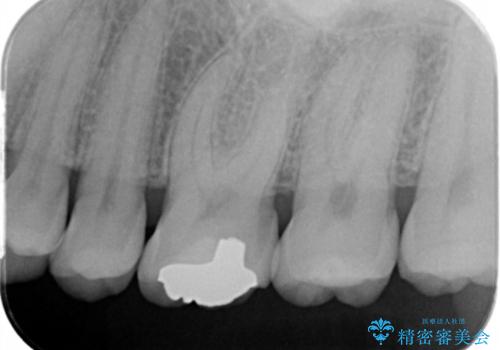

- 昔他院で虫歯治療をしたところが虫歯が再発したとのことで来院。

古い材料(プラスチックの樹脂)をとり、拡大鏡下で虫歯を全て取り除き、

ゴールドインレーにて治療しました。

歯の外側の面が少し欠けていて、そこの部分を覆う(ゴールドの範囲が広くなる)か

そこの欠けてる部分は虫歯ではないので削らないで、最小限にして詰め物を作るか相談したところ

欠けているところは何十年も昔から欠けていて特に何もない。なるべく歯を削りたくないとの事だったので

最小限で詰め物の治療をしました。

インレーについて

ゴールドの詰め物は歯質との隙間ができにくく

虫歯の再発リスクが少なくなります。